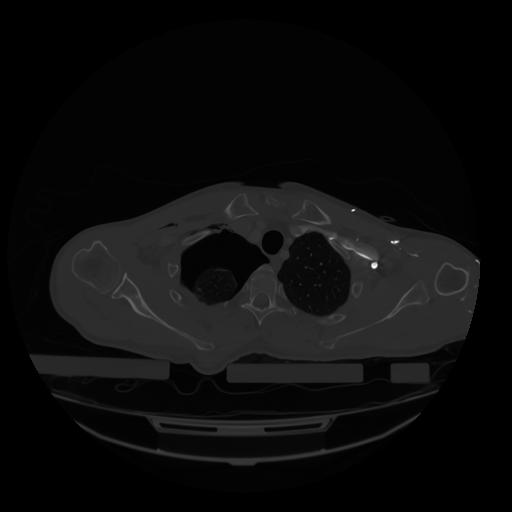

28 CUERPO,CE,Vol,2.0,CUERPO,,